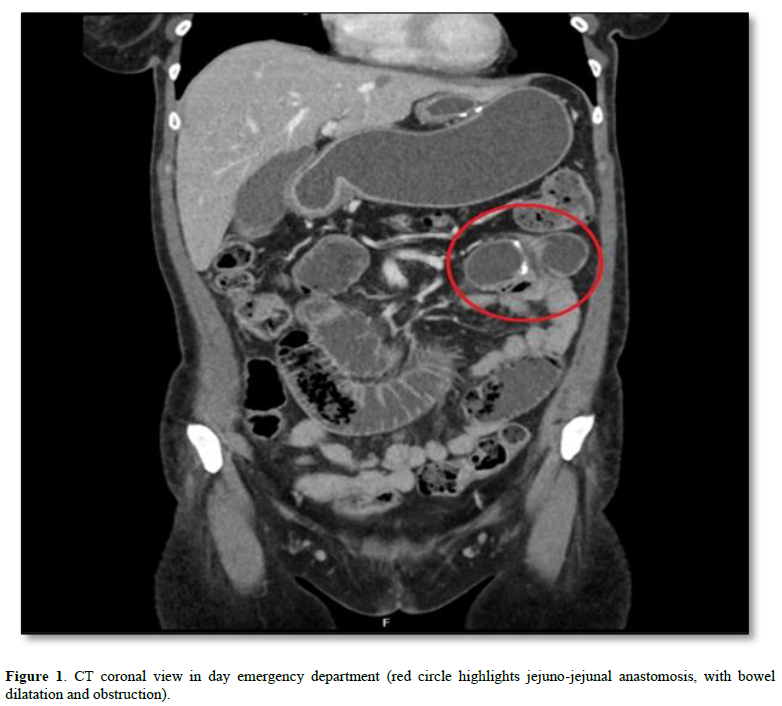

A CT scan of the abdomen and pelvis was performed (Figure 1), identifying distension of the alimentary and biliary loops. As a result, urgent exploratory laparoscopy was performed.

Intraoperatively, no perforation of hollow viscera or internal hernia was found. The common loop was distended near the jejuno-jejunal anastomosis, conditioned by an intraluminal “lesion”. An enterotomy was performed with identification and extraction of a phytobezoar (2 orange segments), which was extracted, and closure was done transversely with barbed suture (Figure 2). The postoperative period progressed favorably, with discharge on the 4th day postoperatively. However, a new admission occurred 15 days later due to a peri-gastric abscess, treated with intravenous antibiotics.